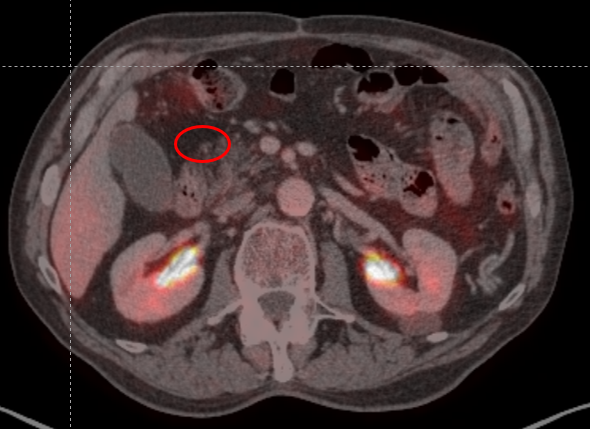

Полный регресс (ПЭТ/КТ от 28.10.2024, 18.02.2025; 08.10.2025).

ПЭТ/КТ от 18.10.2025 полный регресс опухоли